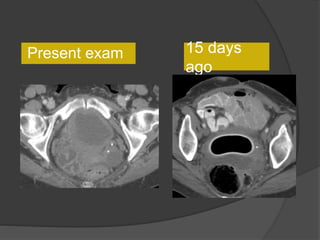

Present exam 15 days ago

Increased size

15 days

ago

Present exam

Case 1 Diagnosis: Recurrent metastatic disease

with mucinous ovarian tumor

64F, abdominal distention, pain, h/o

SBO

• Multilobulated cystic lesion in

the lesser sac and extending

along the adjacent peritoneal

spaces and ligaments

• Cystic lesion in the left

hemipelvis

• Minimal ascites, omental and

mesenteric thickening

15 days ago

Diagnosis: Recurrent metastatic disease

with mucinous tumor